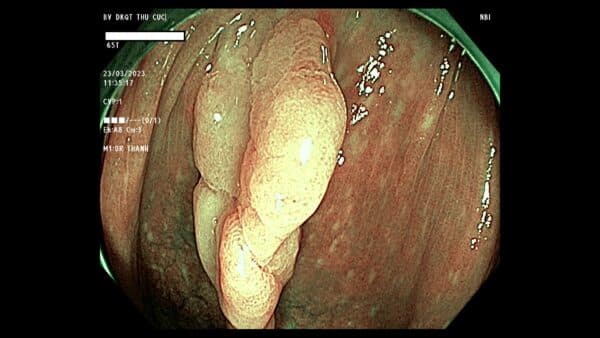

Hình ảnh một polyp đại tràng qua màn hình nội soi.